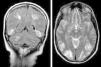

Es dado de alta a los 52 días de hospitalización con resolución de la clínica. RMN de cráneo de control ambulatoria tras 12 semanas de la clínica que es normal (fig. 2).